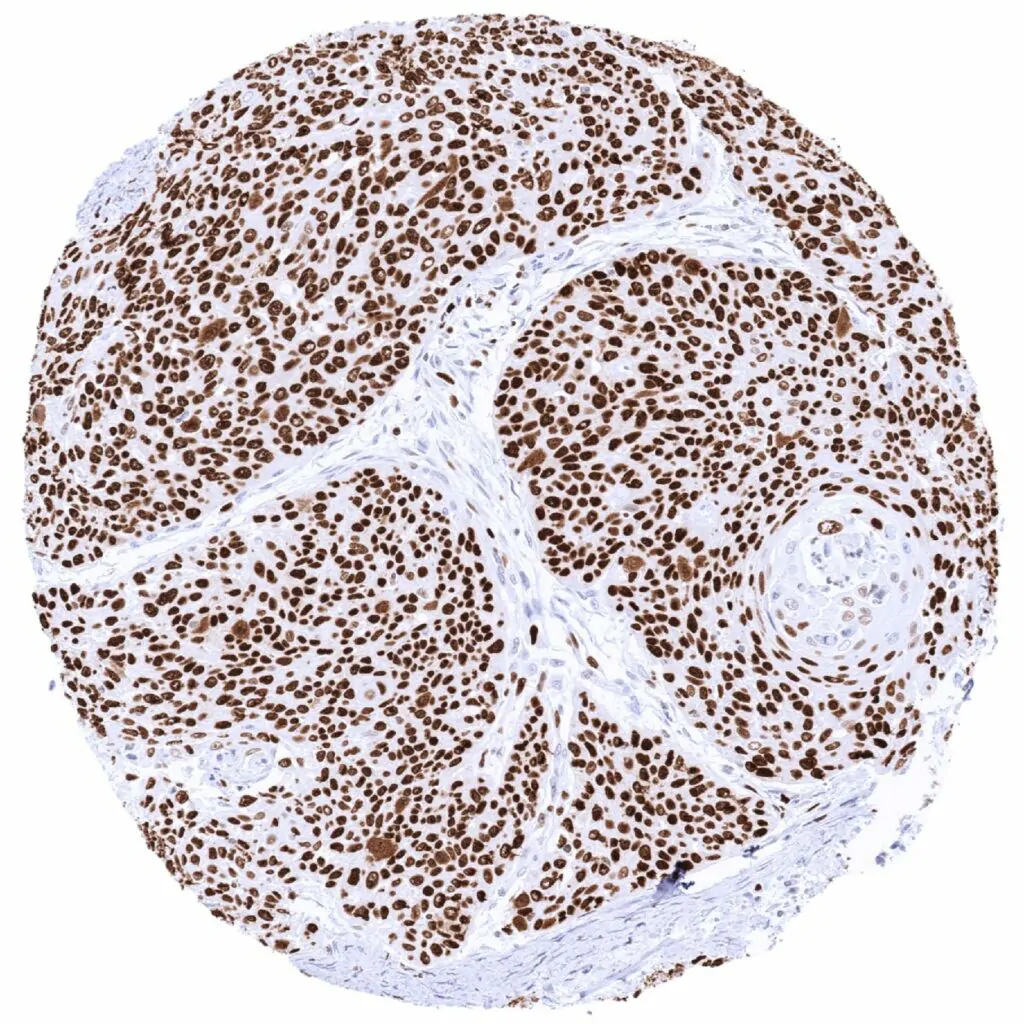

Urinary bladder – Muscle-invasive urothelial carcinoma with strong MCM2 staining of all tumor cells